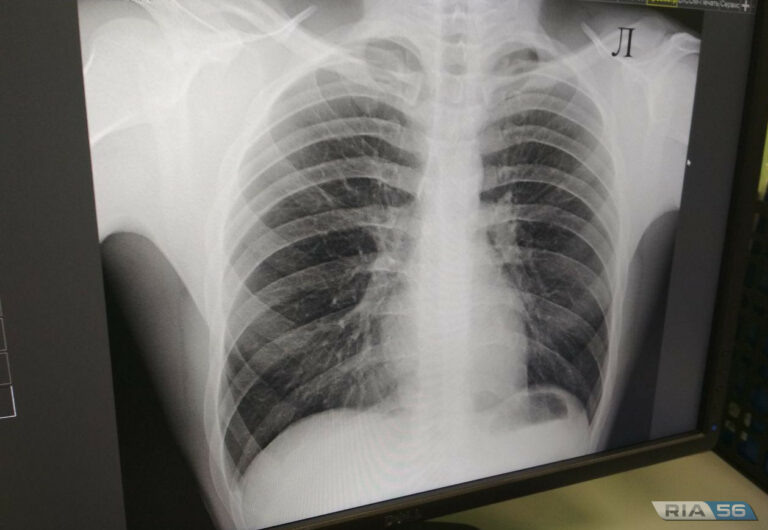

Сегодня, 24 марта — Всемирной день борьбы с туберкулезом. В региональном Роспотребнадзоре напомнили о профилактики данного заболевания. Также рассказали, что начиная с 2008 года в Оренбургской области отмечается тенденция к снижению уровня заболеваемости туберкулезом. — Показатель заболеваемости в 2024 году составил 38,84 на 100 тыс. населения, что на 11,7 % ниже 2023 года, — отметили в надзорном ведомстве. В Роспотребнадзоре напомнили, что основными мерами, направленными на предупреждение распространения туберкулёза, являются: — иммунизация детского населения, — раннее выявление и лечение больных и инфицированных лиц, — проведение противоэпидемических мероприятий в очагах туберкулёзной инфекции. 16+